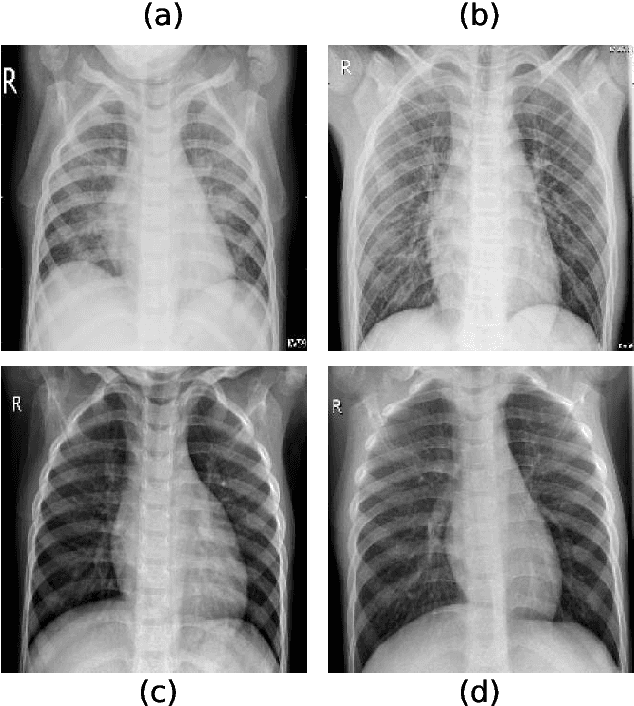

Abstract:Chest radiography is a relatively cheap, widely available medical procedure that conveys key information for making diagnostic decisions. Chest X-rays are almost always used in the diagnosis of respiratory diseases such as pneumonia or the recent COVID-19. In this paper, we propose a self-supervised deep neural network that is pretrained on an unlabeled chest X-ray dataset. The learned representations are transferred to downstream task - the classification of respiratory diseases. The results obtained on four public datasets show that our approach yields competitive results without requiring large amounts of labeled training data.